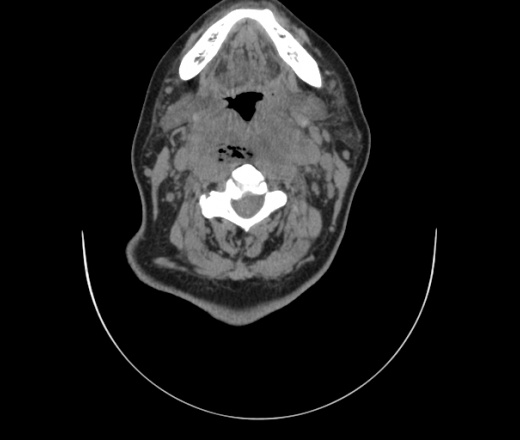

Женщина поступила в х/о спустя 4 дня после того как при употреблении карася подавилась костью.

Наличие газа в средостении на протяжении тел С2-С6 (медиастинальна эмфизема); рыбная кость на уровне тела С6.

При всем уважении, но говорить о медиастинальной эмфиземе, оценивая мягкие ткани шеи, как-то слишком резко. На мой взгляд, это ретрофарингеальное пространство.

Эвакуировали почти 100мл гноя. Но кость не смогли найти. Думаю что она даст дальнейшее ослоднение. Эндоскопически за черпалонадгортаной звязкой не смогли зайти в пищевод, все мягкие ткани отечные, просвет пищевода сдавлен. По всей видимости параэзофагеальная клетчака тоже задействована. Эмпиема, если ее можно так назвать, незнаю как правильно дошла до уровня яремной вырезки. Чем закончиться напишу. Ждем медиастинита.

Флегмона заглоточного пространства шеи, только операция, флегмоны вскрывают. Риск медиастинита.

Согласен с Вами; конечно, наличие газа в клетчатке ретрофарингеального пространства (затмение с опечаткой..). К сожалению, процесс "продвигается" к медиастиниту. Но почему никто, не отмечает наличие рыб. кости; или это для Всех очевидно?

Так вы уже отметили. Хотя ориентировал бы не скелетотопически, а на перстнечерпаловидный сустав.

Кость то мы сразу выявили, размеры где то 17*2мм, но ее так и не получается найти в этой каше